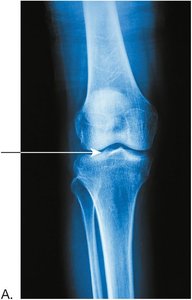

Osteoarthritis and Rheumatoid Arthritis

Osteoarthritis is a chronic inflammatory disease of joints, especially weight-bearing joints, characterized by cartilage degeneration and bone spur formation. Rheumatoid arthritis is an autoimmune disorder causing inflammation and deformity of joints, most often in the hands and feet.

Normal knee joint x-ray Knee joint with osteoarthritis, showing narrowed joint space and malalignment Hands with severe joint deformities from rheumatoid arthritis